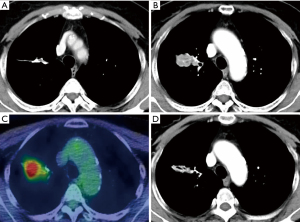

Three of benign granuloma cases showed a tendency to progress, of which 2 cases were at 24 months after surgery and 1 case was at 30 months after surgery. All cases were decreased on the subsequent CT. Figure 4 shows an example of a staple line granuloma case. In this case, a linear thickening had been observed on CT from 6 months after surgery (Figure 4A). A nodular thickening was seen on CT 24 months after the surgery (Figure 4B), and abnormal accumulation was observed on PET-CT (Figure 4C), but it decreased on CT 2 months later (Figure 4D).